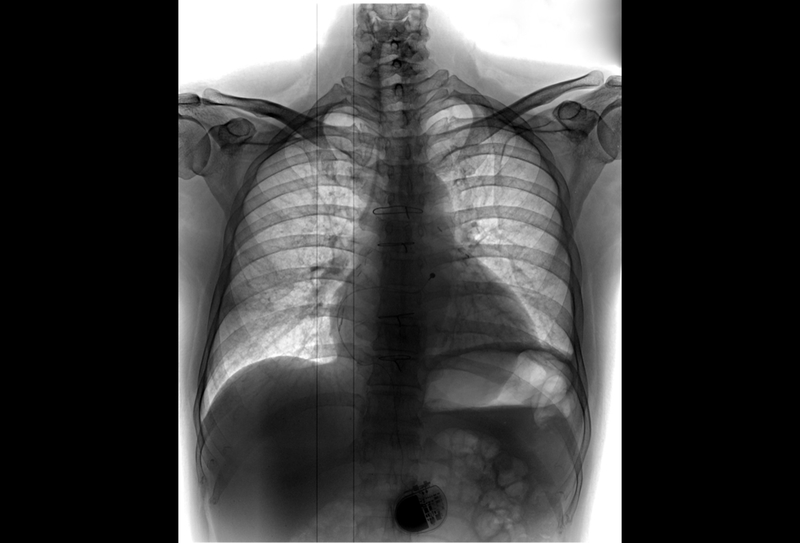

This study helps in providing a framework for monitoring patients with epicardial pacemakers or defibrillators and identifying those who may need revision or removal of their epicardial wires. Dr. Mah and colleagues compared three screening techniques. They recommend that pediatric patients with epicardial devices should get chest x-rays done every few years to assess how their wires look in relation to their heart, as the positioning may change with the child's growth.

They found that a chest x-ray had a high specificity and was a good screening tool, easy to perform, inexpensive, and non-invasive. However, it can produce some false-negatives even when patients were symptomatic. "The use of pacemakers and defibrillators in children is growing. As more epicardial devices are implanted, more children may be at risk for developing coronary compression from their leads," said Mah.